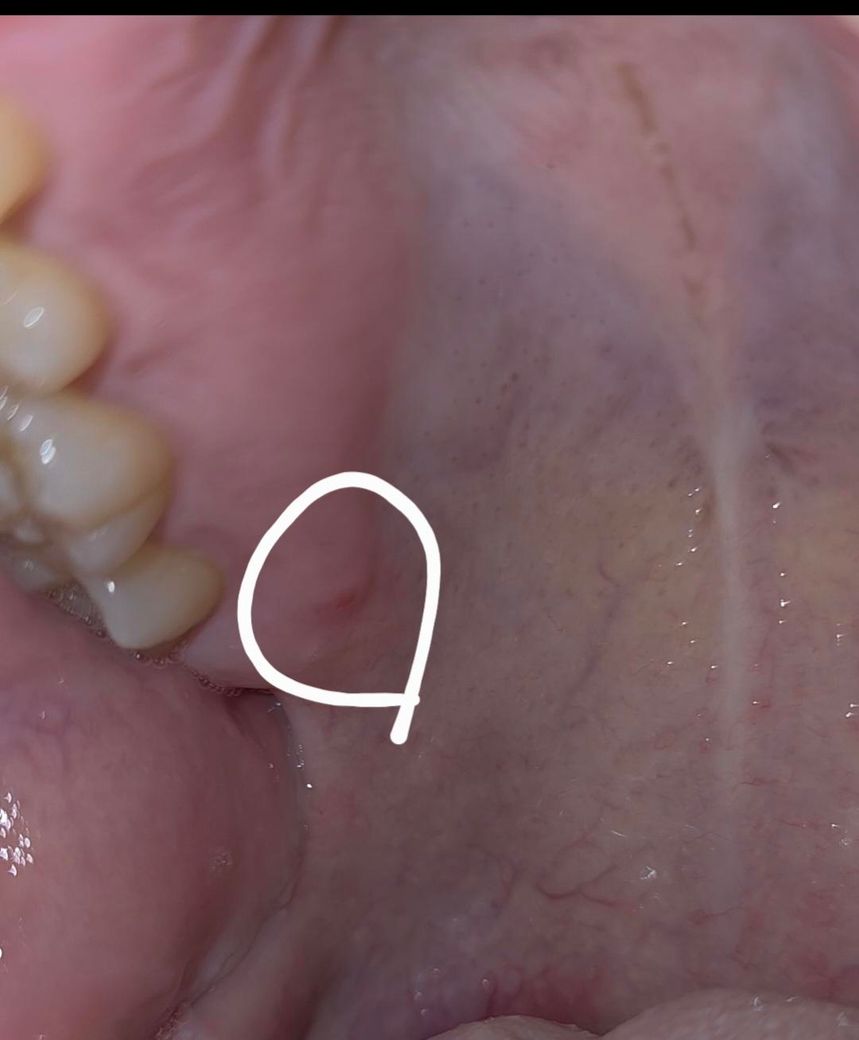

잇몸이라고해야하나 입천장이라고 해야하나요 ..이게뭐죠??..

어느순간부터 나잇는데 딱딱하구요. 건들면 아파요 ..구내염은 아닌거같은데

안없어지는데 치과갈때도 아부위에 언급은 없어서...이게 뭔가요 ㅠㅠ 구강암같은건 아니겟죠??ㅠㅠ

입천장에 상처가 생긴거 같습니다 큰 문제가 잇는건 아니니 크게 걱정은 안하셔도 될것같습니다.

잇몸이나 치아에서 비롯된 염증의 양상일 수 있을 것 같습니다. 해당부위 엑스레이 사진 한번 찍어보면 좋을 것 같습니다.